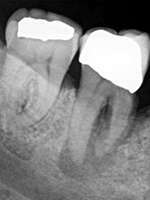

Les couronnes